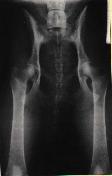

Na levém snímku můžeme vidět kyčelní klouby zdravého

zvířete, ale na druhém snímku je zrentgenované zvíře postižené těžkou

dysplazií.

Posouzení DKK

Vědecká komise FCI sestavila klasifikační schéma, které

rozděluje nálezy na kyčelních kloubech do pěti stupňů. Jednotlivé stupně

DKK označuje písmeny "A" až "F". Mimo tohoto schématu existuje ještě

celá řada systému pro vyhodnocení RTG snímků na DKK. Je to např.

klasifikační schéma společnosti OFA, která člení postižení do 7 stupňů.

Anebo Pensylvánský systém PennHIP. U nás se posuzuje podle

klasifikačního schématu, které vychází ze schématu FCI. Používá se

označení stupňů 0-4. Přičemž nulou (A) se označuje ideální stav. Čísla

1-4 (B - E) označují různé stupně postižení - přičemž čím vyšší číslo

(písmeno) tím závažnější postižení psa.

Podkladem pro určení dyspalzie je měření úhlu dle

Norberga (objektivní měřítko posuzování). Dalšími parametry jsou např.

pozice středů hlavic, kongruence (souběžnost) kloubních ploch nebo i

postižení kloubu sekundárními artrotickými změnami.